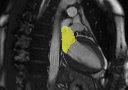

GTnnUNetUNETR+Ours SA/LA onlyOurs AllRefer to captionRefer to captionRefer to captionRefer to captionRefer to captionRefer to captionRefer to captionRefer to captionRefer to captionRefer to captionRefer to captionRefer to captionRefer to captionRefer to captionRefer to caption

Figure 3: Qualitative segmentation results among nnUNet, UNETR+, and the proposed methods. UNETR+ and the proposed approach in the last column (Ours All) use all sparse CMR sequences as network input, while nnUNet and the second last column (Ours SA/LA) are trained solely with either SA or LA views.